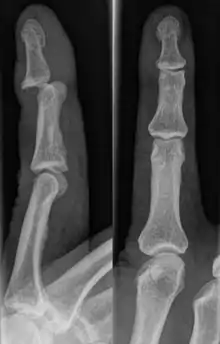

Dislocations can be categorised based on location and type. The finger can be split into three bones and two joints in an alternating order. From the fingertip to the knuckle, these are as follows; distal phalanx, distal inter-phalangeal (DIP) joint, middle phalanx, proximal inter-phalangeal (PIP) joint, and proximal phalanx. DIP dislocations are much less common than PIP dislocations,[2] due to the “stability provided by strong collateral ligaments, palmar plates, and tendinous insertions, as well as the short lever arm of the distal phalanx”.[7] Dislocations can be categorised based on the direction that the fingertip moves in relation to the knuckle, be it in the direction of the palm (volar dislocation), or the direction of the back of the hand (dorsal dislocation). Of the two, dorsal dislocations are more common.[3] If reduction has been attempted, an x-ray of the dislocation should appear concentric if successful.[2] However, if there is a fracture present, there will be a misalignment of the joint, which will be evident from the radiograph.[2] Bach suggests a referral to a hand surgeon if a misalignment is present.[2]

Fractures are instances where the bone's structural integrity has been compromised. This is indicated by midshaft pain, as well as visual midshaft angulation or rotation.[3] As with any skeletal injury, an x-ray can be conducted to verify the presence of a fracture.[1] The distal phalanx is especially vulnerable to avulsion fractures, where a fragment of bone is ripped off when the tendon separates from the phalanx.[1] Avulsion fractures are especially common following a first time dislocation.[1] These are especially concerning, as it may indicate a complete tear of the extensor digitorum tendon. If left untreated, this may lead to permanent DIP extensor lag (inability to fully straighten the finger).[8]